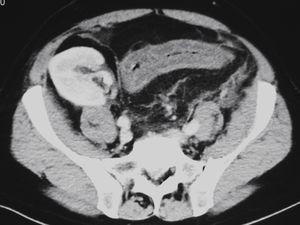

Durante el ingreso se instauró tratamiento médico y antibiótico empírico de amplio espectro, sin mejoría clínica. Los coprocultivos, parásitos y toxina de C. difficile en heces resultaron negativos, al igual que la antigenemia, la PCR y el cultivo de CMV5. La tomografía axial computarizada (TAC) abdominal sin contraste (figura 1 y figura 2) mostró imágenes compatibles de colitis aguda recto-sigma. Ante la sospecha de posible proceso vascular, se solicitó estudio de anticoagulación, homocisteína y anticuerpos anticardiolipina, que fueron negativos, y se inició tratamiento con heparina de bajo peso molecular.

Figura 1. Tomografía axial computarizada abdominal.